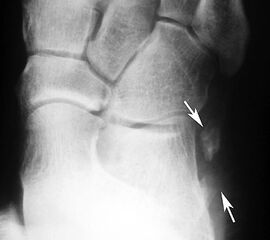

Frakturiertes Os peroneale. Das proximale Fragment ist am Fußaußenrand neben dem Calcaneus erkennbar, das distale Fragment liegt noch in Höhe des Cuboidtunnels.

Abbildung 5

Die klassischen Röntgenaufnahmen des Sprunggelenks in zwei Ebenen und des Fußes in drei Ebenen unter Belastung dienen vor allem dem Ausschluss der verschiedenen Differentialdiagnosen. Weiterhin können knöcherne Verletzungen der Gleitrinne oder auch eine Ruptur der Peroneaus longus Sehne mit disloziertem Os peroneum dargestellt werden. Besteht der Verdacht auf ein kleineres Knochenfragment oder besteht gleichzeitig eine Fraktur, so kann in Ergänzung ein hochauflösendes CT durchgeführt werden 7.